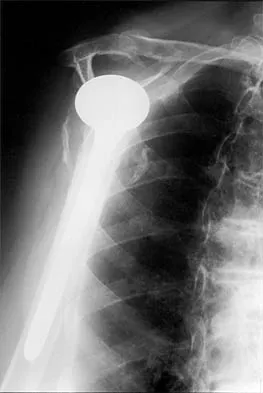

Figure 36a shows the current radiograph of a 65-year-old woman who slipped and fell. History reveals that prior to the fall she was actively functioning without pain. Figure 36b shows a radiograph obtained 1 year ago. Based on the fracture pattern, the failure is most likely related to

The radiograph shows a fracture distal to the prosthesis in a stable, apparently well-fixed prosthetic stem. The well-fixed prosthesis-bone composite is stiff, creating a modulus mismatch between the proximal and distal femur. Therefore, the risk of fracture, particularly in osteoporotic bone, is increased at this level. Revision of the stem to a longer construct is unnecessary, and standard plate and screw fixation has been shown to yield union rates of greater than 90%. Nonsurgical treatment of fractures distal to the tip of the prosthesis results in high nonunion rates, reported to be from 25% to 42%. Johansson JE, McBroom R, Barrington TW, Hunter GA: Fracture of the ipsilateral femur in patients with total hip replacement. J Bone Joint Surg Am 1981;63:1435-1442. Bethea JS III, DeAndrade JR, Fleming LL, Lindenbaum SD, Welch RB: Proximal femoral fractures following total hip arthroplasty. Clin Orthop 1982;170:95-106.